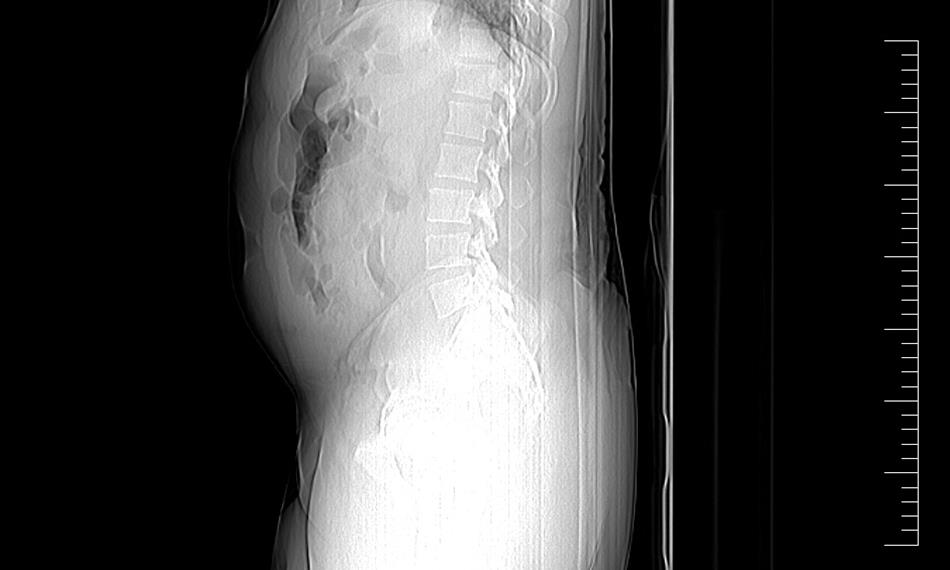

Minulý týden opět celníci na letišti Václava Havla v Praze Ruzyni odhalili pašeráka – polykače. Tentokrát se jednalo o 39letého nigerijského státního příslušníka, který postupně vyloučil 19 kapslí obsahujících drogy. Cizinec cestoval na pravidelné lince Madrid-Praha.

Ke kontrole byl polykač celníky vytipován na základě provedené rizikové analýzy daného letu. Prvotní podezření na pašování drog celníkům potvrdily kontrolní stěry z rukou pašeráka.

Postupně z těla pašeráka vyšlo všech 19 kontejnerků naplněných bílým práškem. Chemická látka při provedení detekční zkoušky pozitivně reagovala jako kokain. Celková hmotnost všech kapslí včetně drogy je 211,4 gramů. Určení vlastní hmotnosti a druhu zajištěné drogy je předmětem další odborné expertízy. Podle zkušeností celníků se s největší pravděpodobností jedná o velmi koncentrovaný kokain. Zda byla droga určena na český trh nebo k distribuci v jiné zemi, je předmětem dalšího šetření.